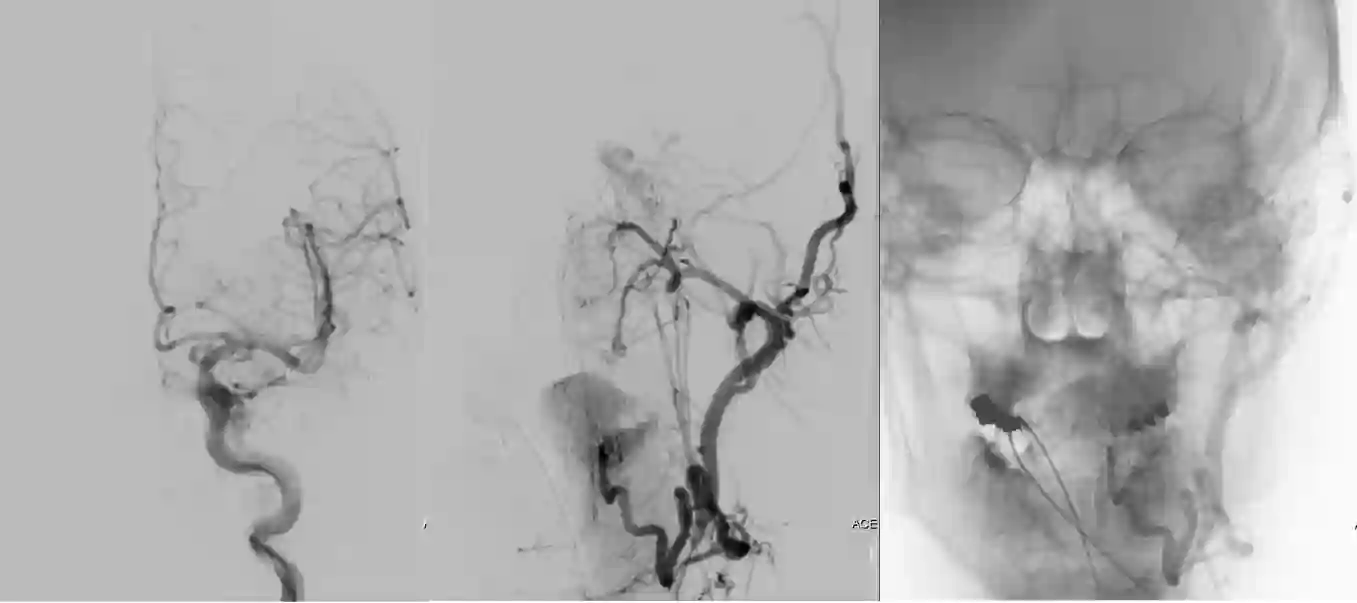

Der Goldstandard in der Diagnostik von CC-Fisteln ist eine digitale Subtraktionsangiographie.